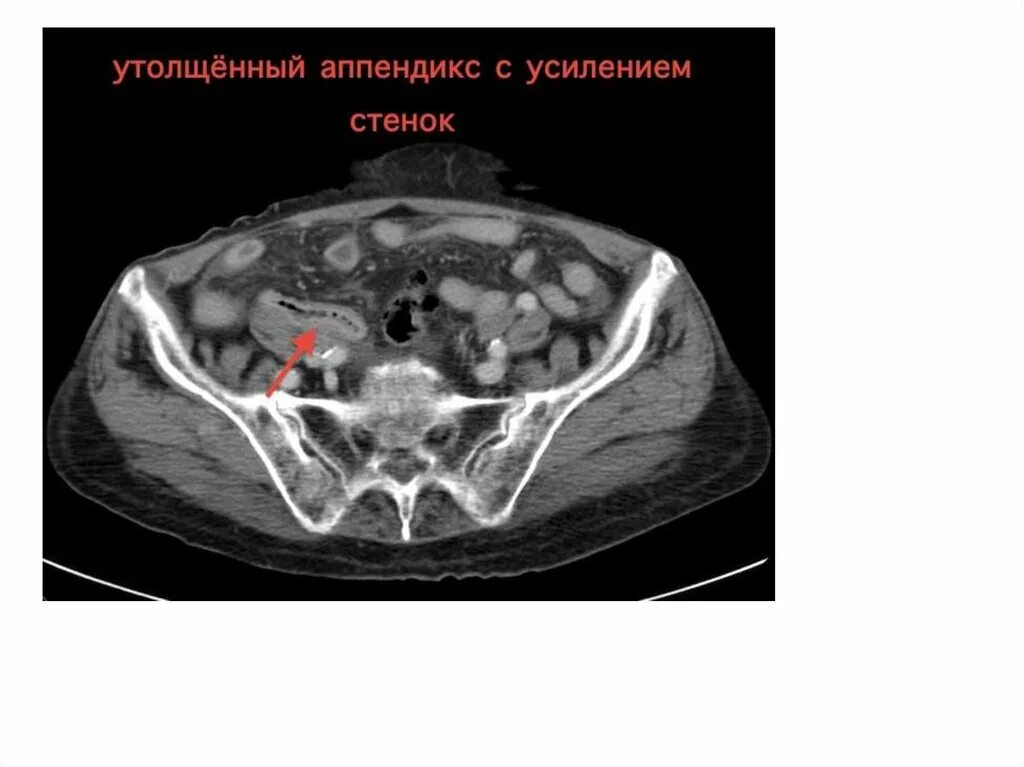

Малом тазу аппендицит